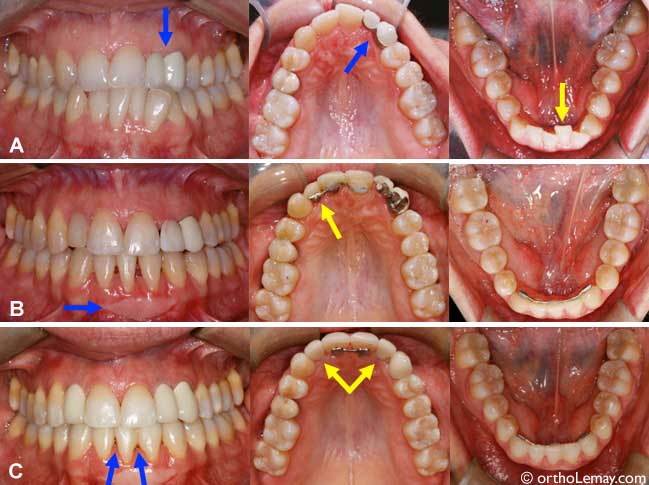

Le cas MC: après l’orthodontie

Un an après l’orthodontie, les restaurations finales sont en place; facettes sur plusieurs dents supérieures, les couronnes sur implants sont posées et une prothèse partielle amovible remplace les dents manquantes inférieures.

(A) Malocclusion avec occlusion croisée antérieure et usure importante sur certaines incisives.

(B) À la fin des corrections orthodontiques; les dents antérieures sont dans une position plus fonctionnelles qui minimisera les chances d’usure à long terme. La mandibule est reculée en relation normale par rapport au haut. Les espaces édentés seront comblés par des couronnes sur implants. Les flèches indiquent les implants qui sont prêts à recevoir les couronnes.

(C) Après restauration des incisives usées par le dentiste à l’aide de facettes.